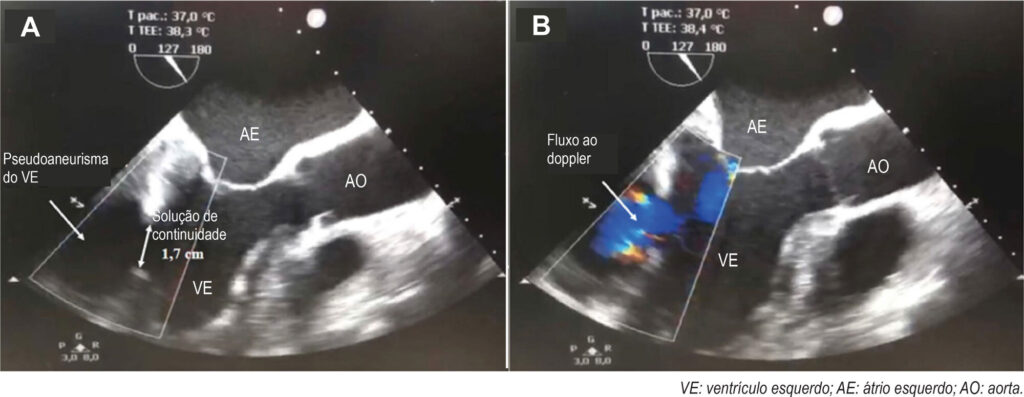

Pseudoaneurisma Ventricular Esquerdo em Paciente Diabético sem Clínica de Síndrome Coronariana Aguda

O pseudoaneurisma do Ventrículo Esquerdo (VE) consiste em uma ruptura da parede livre, que é contida pelo pericárdio adjacente. É uma patologia grave e de alta morbimortalidade que, geralmente, surge como complicação do Infarto Agudo do Miocárdio (IAM). O quadro clínico pode ser inespecífico e, em algumas situações, o paciente é assintomático, o que pode dificultar o diagnóstico.– Em razão do risco elevado de ruptura e tamponamento cardíaco a correção cirúrgica é o tratamento de escolha.,

Relata-se o caso de paciente portador de Diabetes Mellitus (DM), com história prévia de transplante renal, imunossuprimido e assintomático, que teve o diagnóstico incidental de pseudoaneurisma do VE.